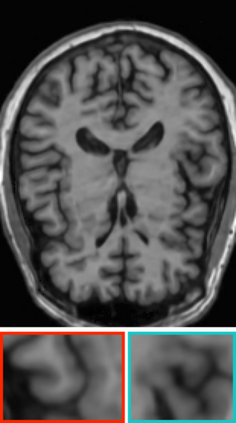

Deep neural networks for medical image reconstruction are traditionally trained using high-quality ground-truth images as training targets. Recent work onNoise2Noise (N2N) has shown the potential of using multiple noisy measurements of the same object as an alternative to having a ground truth. However, existing N2N-based methods cannot exploit information from various motion states, limiting their ability to learn on moving objects. This paper addresses this issue by proposing a novel motion-compensated deep image reconstruction (MoDIR) method that can use information from several unregistered and noisy measurements for training. MoDIR deals with object motion by including a deep registration module jointly trained with the deep reconstruction network without any ground-truth supervision. We validate MoDIR on both simulated and experimentally collected magnetic resonance imaging (MRI) data and show that it significantly improves imaging quality.